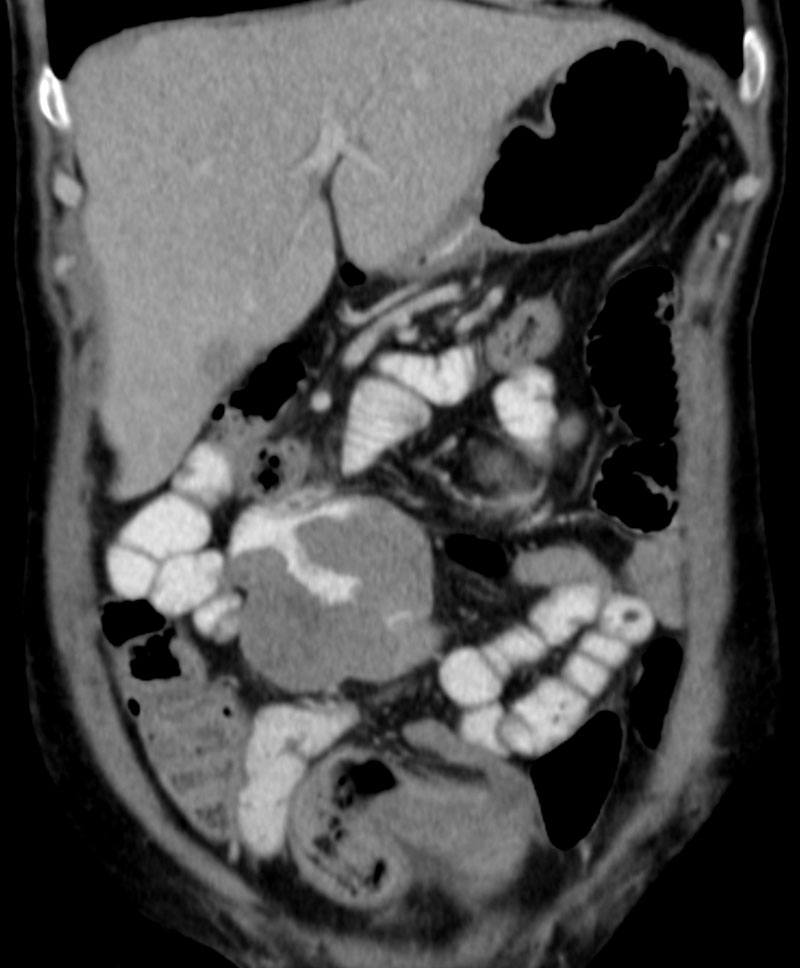

Di căn ruột non

» Thông tin: Nữ giới – 56 tuổi.

» Lâm sàng: Đau bụng.